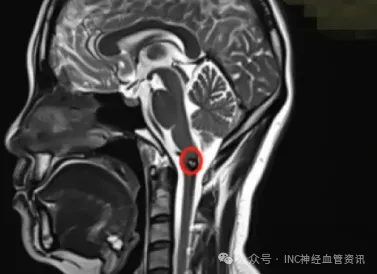

面瘫、斜视、偏瘫,脑桥海绵状血管瘤手术为何步步惊心?

脑干脑桥海绵状血管瘤一旦出血,后果不堪设想。手术切除是根治病灶的希望所在。然而,手术风险极高,稍有不慎便可能伤及重要神经,如何选择最安全的手术入路,是神经外科领域持续探索...